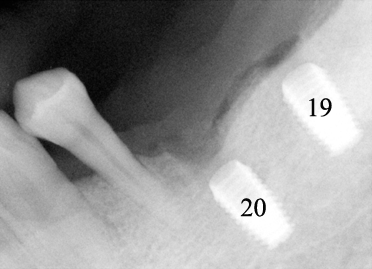

Fig.3 When the pan in Fig.2 was taken, the

patient requested more implants in the lower left quadrant. To

reduce thread exposure, we planned to place 2 implants (8 mm long) (#19 (pink tracing

line) and 20 (yellow) on the either side of the mental nerve and below the

ridge. These 2 implants should be above the inferior alveolar nerve

and incisive nerve, respectively. #20 implant should avoid touching

the neighboring root. An alternative was proposed to extract #21,

place implants at #19 and 21, and fabricate 3-unit fixed prosthetic

denture. The patient declined.

Notice the angulation of the implant for #20. |